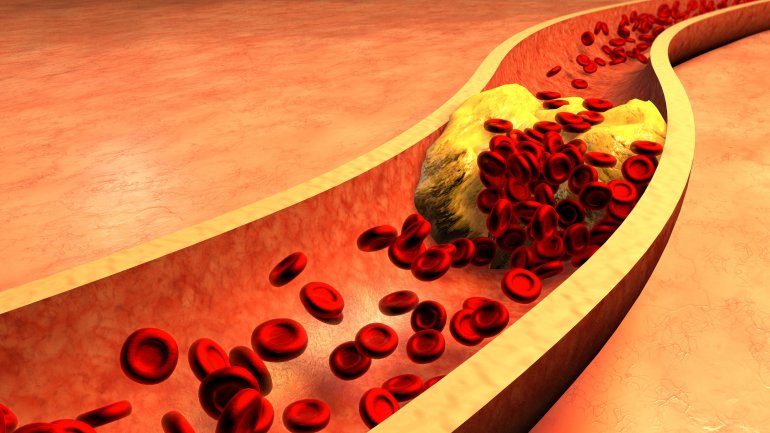

Η γυμναστική με βάρη για λιγότερο από μία ώρα την εβδομάδα μπορεί να μειώσει τον κίνδυνο για καρδιακή προσβολή ή εγκεφαλικό επεισόδιο κατά...